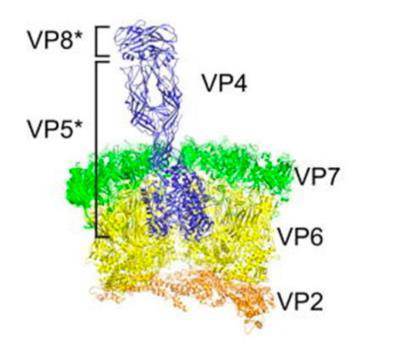

Reoviruses (呼吸道腸道病毒)

-

ds RNA

- 多段

-

double-layered capsids

- 20 面

- intermediate/ infectious subviral particle (ISVP)

- 中外層的capsid (σ3/VP7)在腸道被蛋白酶分解

- σ1/VP4 被切割產生 ISVP

- VP4 → VP5,VP8

-

無套膜

- 先去 ER 再裂解

-

丟 RNA(+)出來做蛋白

- 口糞傳染

Orthoreovirus 會感染人類,所以 Reoviruses 就是 Orthoreovirus,而 Reoviridae 指所有

Rotavirus(輪狀病毒)

- 11段 RNA